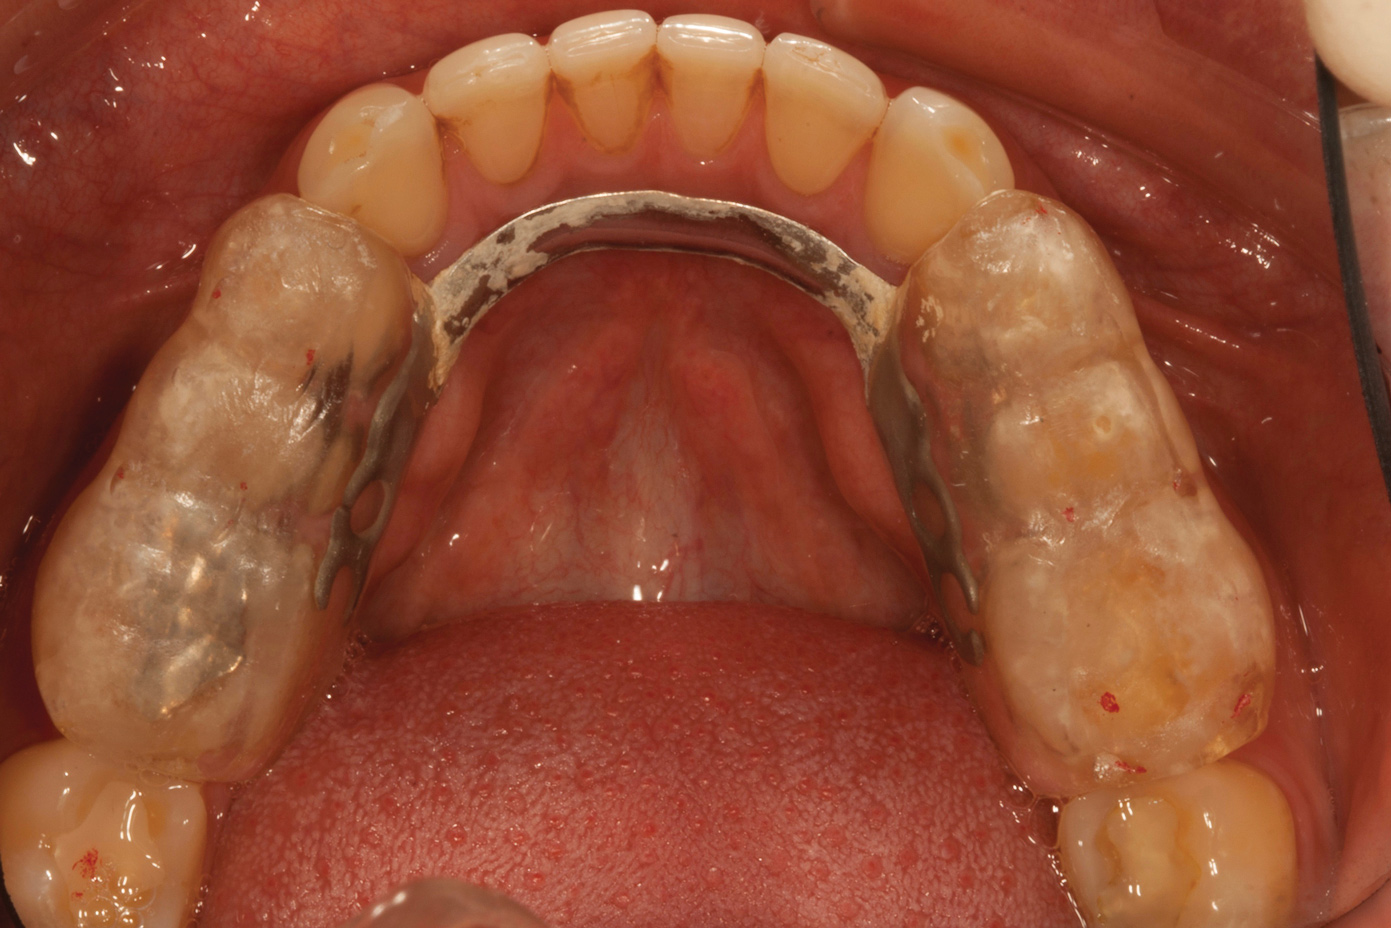

Over time, the patient had developed joint and muscle symptoms due to his lack of posterior support and sought the help of a specialist. His bite was analyzed, and he was fitted with a dental orthotic that allowed his teeth to touch in centric relation (Figure 3). This was intended to be a temporary measure to stabilize the patient's bite and make him comfortable, but before any permanent treatment could be carried out, he moved abroad and had been living with the device for more than 4 years before the time of the consultation. He stated that his bite was now very stable with the orthotic, but he was looking for a more permanent solution and also wanted to improve the overall appearance of his smile.

A comprehensive examination was carried out, and preoperative photographs were taken (Figure 1 through Figure 4). The patient presented with fair oral hygiene and slight, generalized tissue inflammation. Caries and defective restorations were detected on teeth Nos. 4, 5, 13, and 14. The crown on tooth No. 12 was showing signs of leakage, and although the endodontic access cavity had been temporarily restored with composite, this endodontic re-treatment was acceptable and the tooth was otherwise symptom-free. Erosion was present on most of the posterior teeth and the cuspids, and abrasion was noted on teeth Nos. 4, 5, 10, 11, 20, 21, 22, 28, and 29. An examination of the patient's muscles, joints, and bite revealed no joint sounds, a normal range of motion, and negative joint load and immobilization tests.

The patient's removable dental orthotic covered the lower bicuspids and first molars. With the orthotic in place, there was shim stock contact on all posterior teeth and on the second molars that were not covered by the appliance. However, there was no incisal overlap and a lack of anterior guidance.9When the orthotic was removed, no more than three teeth touched, and a 2-mm space between the posterior teeth made mastication difficult.

Fig 3. Preoperative occlusal view of lower arch with orthotic in place.

Figure 3